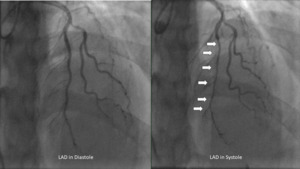

Given her age, she first underwent computed tomography coronary artery imaging which demonstrated a long intramuscular segment of the left anterior descending artery without significant stenosis, separate origin of the left anterior descending and left circumflex coronary arteries from the left coronary cusp without a left main coronary artery, high-grade stenosis of the origin of the 1st diagonal. She then underwent a coronary angiogram which revealed hemodynamically significant myocardial bridging of the left anterior descending (resting-full-cycle-ratio, RFR positive at 0.76) indicative of myocardial ischemia during systole, moderate lesions involving the 1st diagonal (60%) which was RFR negative at 0.93 and 1st/2nd obtuse marginals (30% and 50% respectively) (Figure 1). She was placed on medical therapy with beta-blockers and calcium channel blockers without significant improvement despite 4 weeks of therapy at the highest doses tolerated. A Heart Team approach involving the Interventional Cardiologist, Cardiology Consult Team, Cardiothoracic Surgery, and the patient ultimately resulted in the decision for bypass surgery given her constant, unrelenting symptoms of unstable angina.

Extensive myocardial bridging refers to cases where the tunneled segment of the coronary artery extends over a considerable length (>2.5 cm, and >0.5 cm deep), resulting in significant compression and compromised blood flow.1,7,8This compression during systole can lead to myocardial ischemia and symptoms such as angina, dyspnea, or even myocardial infarction in severe cases.1,2 Coronary angiography remains the gold standard for visualizing systolic compression or “milking” of the coronary artery.4,6 Other methods of assessing systolic compression include intracoronary doppler, intravascular ultrasound, fractional flow reserve, and cardiac computed angiography.4–6